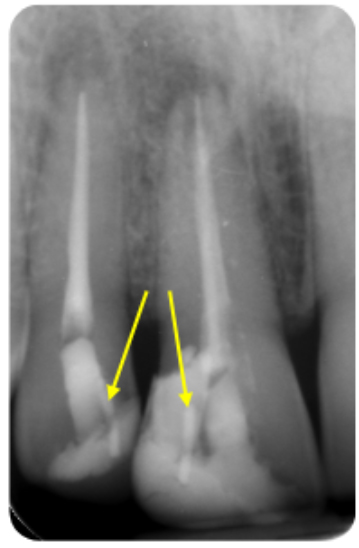

Figure 1: Pulp canal obliteration (PCO). The patient had trauma to UL1 15 years ago and developed a yellow discolouration over time. She was keen to improve the appearance of the tooth. The UL1 was asymptomatic and did not respond to sensibility testing.

Radiographically, UL1 had a normal PDL width and an intact lamina dura could be seen around the tooth. A diagnosis of pulp canal obliteration was reached for UL1. There was no endodontic infection and the patient was advised to have external tooth whitening; this will take longer and a veneer might be necessary if a satisfactory result can’t be achieved with external whitening alone. Figure 1a: Preoperative photograph. Figure 1b: Preoperative radiograph.